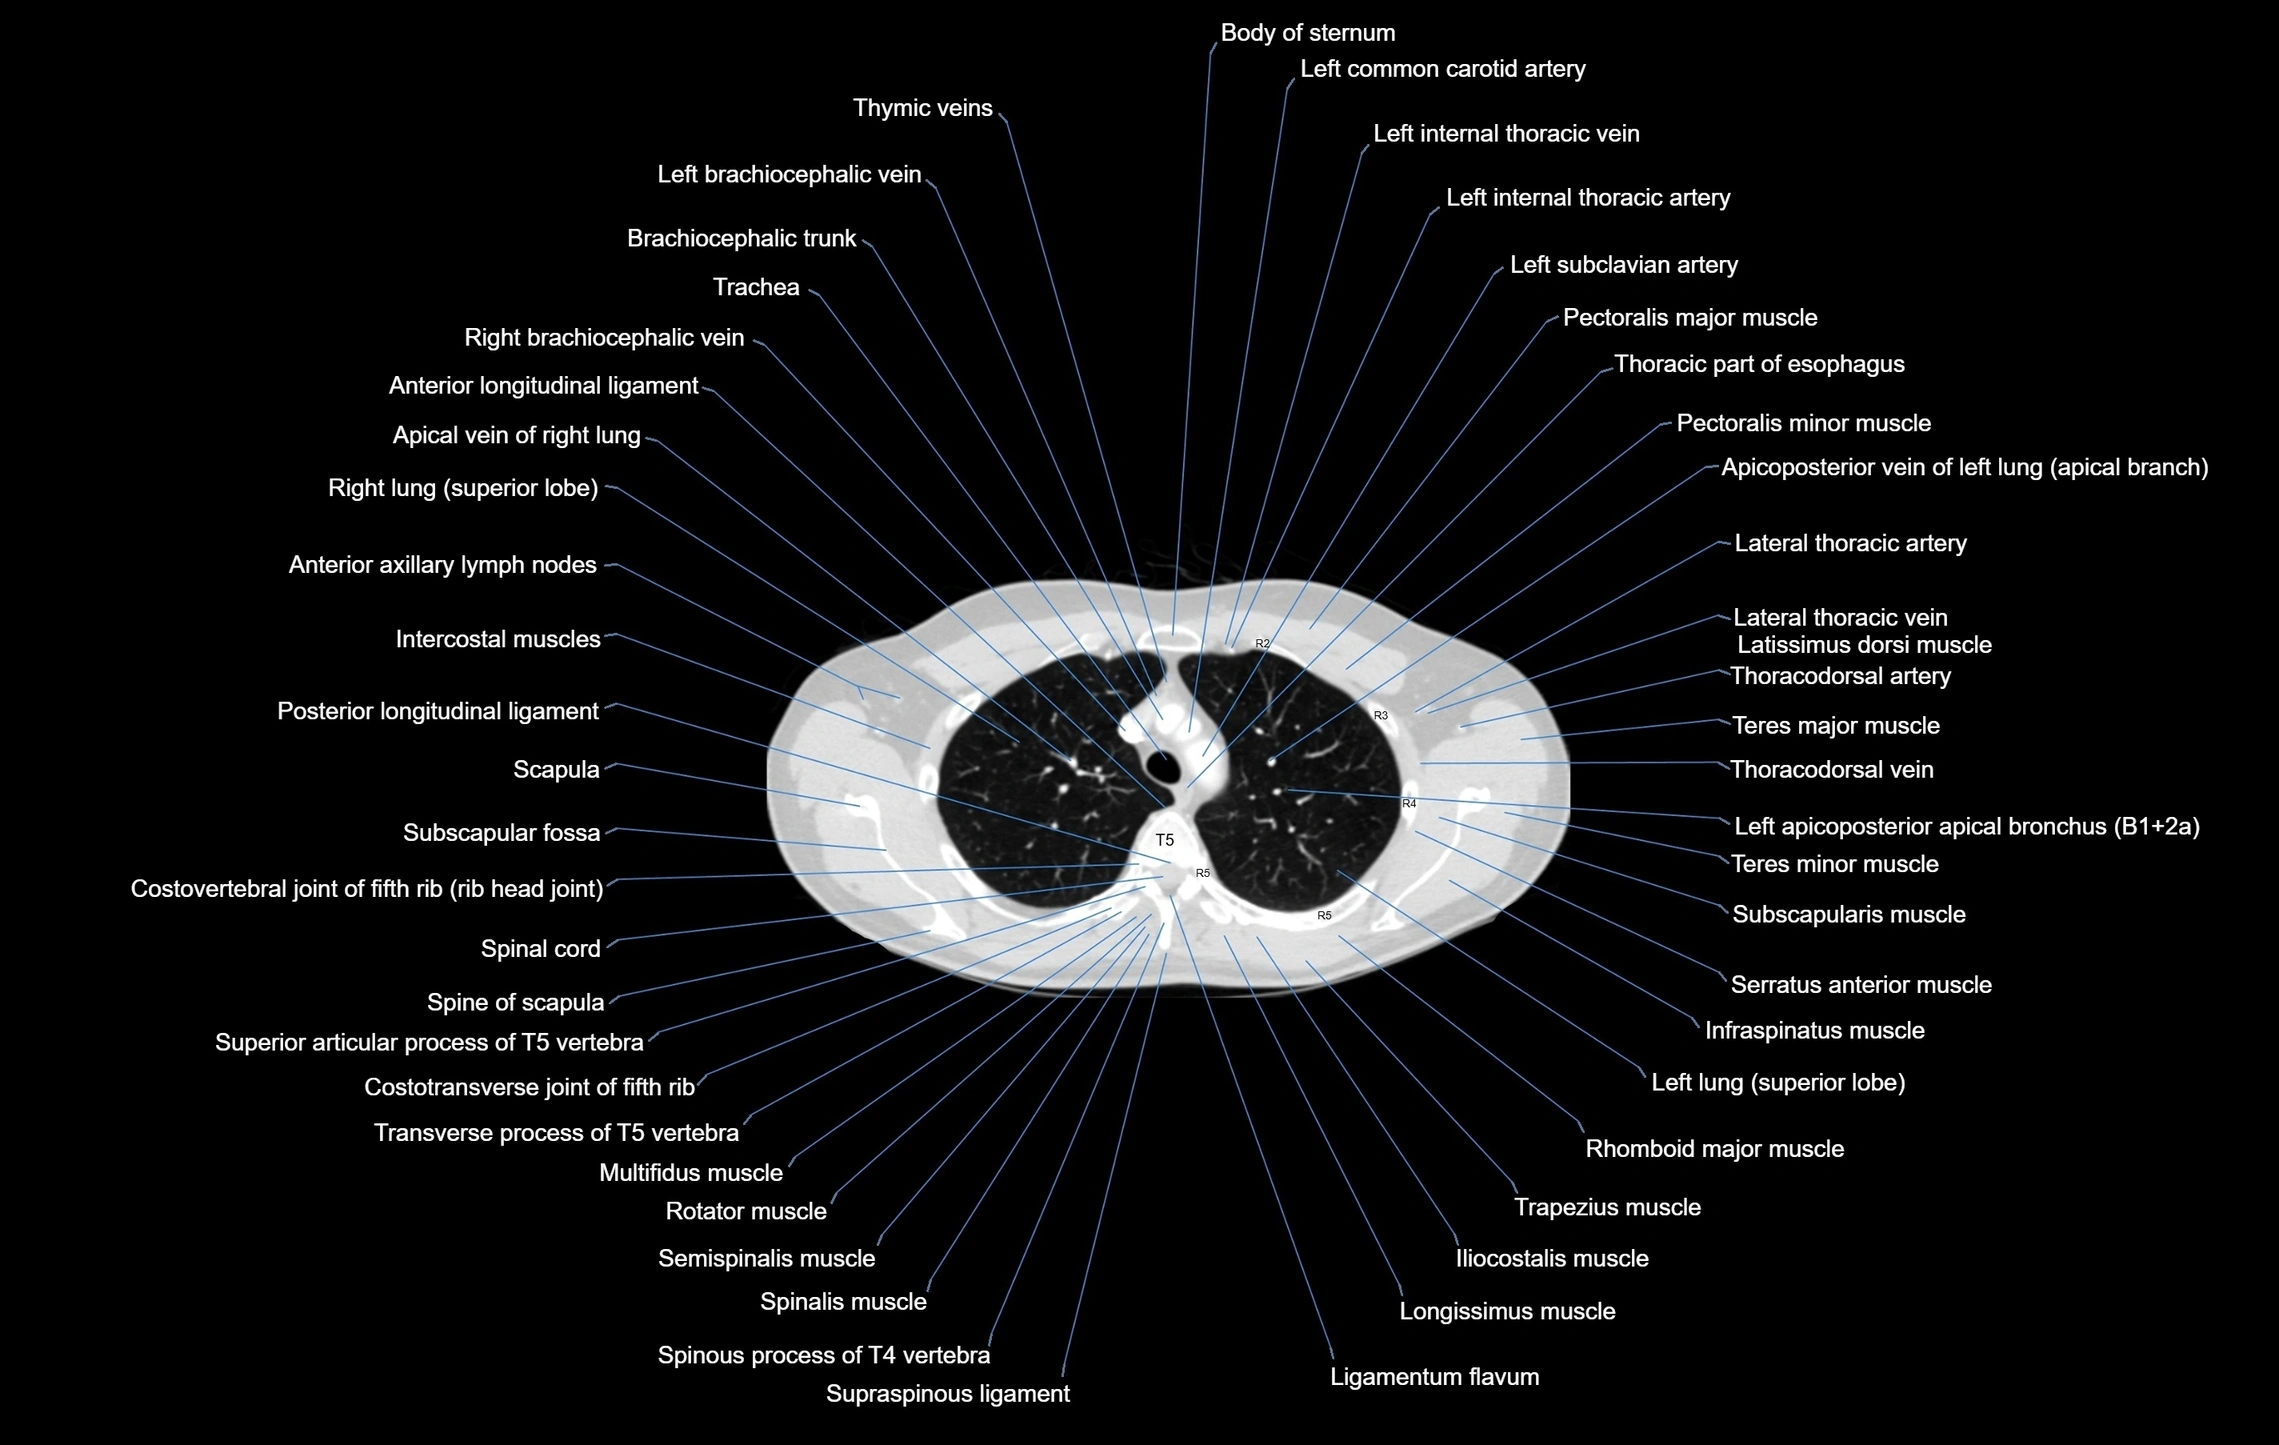

- Anterior longitudinal ligament

- Azygos vein

- Body of sternum

- Brachiocephalic trunk

- Descending thoracic aorta

- Infraspinatus muscle

- Intercostal muscles

- Latissimus dorsi muscle

- Left brachiocephalic vein

- Left common carotid artery

- Left internal thoracic artery

- Left internal thoracic veins

- Left subclavian artery

- Pectoralis major muscle

- Pectoralis minor muscle

- Posterior longitudinal ligament

- Rhomboid major muscle

- Right main bronchus

- Scapula

- Serratus anterior muscle

- Subscapularis muscle

- Teres major muscle

- Teres minor muscle

- Thoracic part of esophagus

- Trachea

- Trapezius muscle